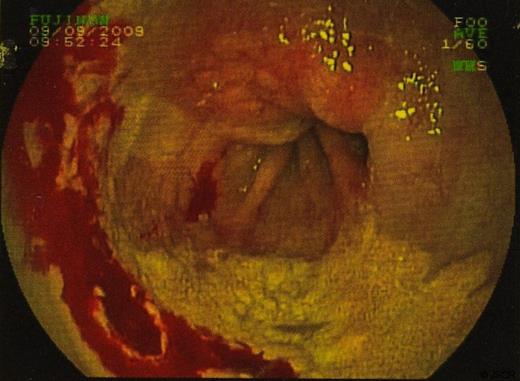

Biopsies were taken and sent to histopathology. In some sections the cells viewed had small bland nuclei with foamy cytoplasm. They were negative for mucin stain and negative for epithelial markers. There was no dysplasia or malignancy. This picture was consistent with xanthalasma. Other biopsies of surrounding tissue showed a picture consistent with Barrett’s oesophagus. (Figure 3 & 4)

Endoscopic ultrasound examination showed an area of xanthalasma proximal to the oesophago-gastric junction in segments of Barrett’s mucosa. There were no enlarged lymph nodes. The gastric mucosa was shown to be diffusely thickened suggestive of Ménétrier’s disease.